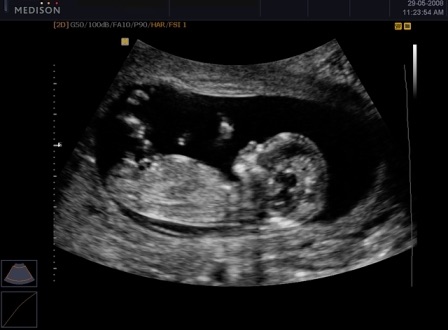

решили пойти за вторым ребеночком. Не думала писать, хотела дождаться результатов, но не могу не поделиться. В этот раз делали без стимуляции в ЕЦ. Созрело 2 фолликула, один из которых не стали даже пунктировать, не дозрел. Один хороший с одной клеточкой. Оплодотворение произошло, слава богу и на третий день было решено делать подсадку. я попросила показать мне мою лапочку на узи. Эта картинка стоит перед глазами

ой спасибо. Ну УЗИ клеточку мне показывали и врач говорит:"Видишь, с косичками, как ты просила" Мы посмеялись от души